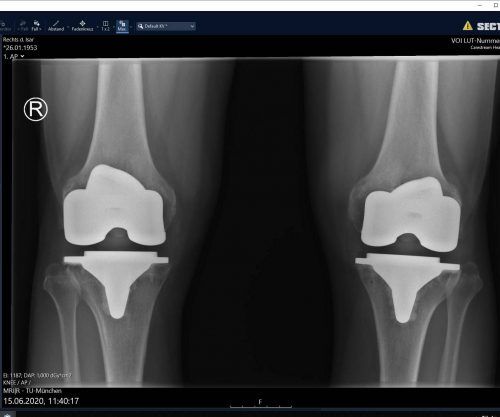

Neue Knie: Jetzt radelt er bis an die Ostsee

Langenbach – Niemand legt sich gerne unters Messer. Aber manchmal kommt man um die OP nicht mehr herum. So wie Wolfgang Klaus aus Langenbach im Kreis Freising. Der 67-Jährige litt an schwerster Arthrose – genauer gesagt an Gonarthrose, wie Mediziner die Verschleißerkrankung des Kniegelenks nennen. „